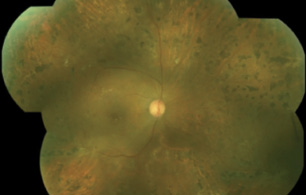

Figure 1. A 27-gauge vitrector is used in aspiration mode to grasp an edge of fibrovascular membrane and lift and peel the tissue.

The vitrector is used in aspiration mode to grasp an edge of membrane or hyaloid and to lift and peel as soon as resistance is encountered (Figure 1). The footpedal is then shifted to cutting mode, and the lifted tissue is removed. This maneuver is sequentially repeated, together with blunt dissection, until only tissue over the optic nerve and around vessels remains. Tissue over vessels can be shaved in cutting mode with minimal aspiration (Figure 2). Tissue over the optic nerve can be peeled using suction with the vitrector at maximum aspiration.